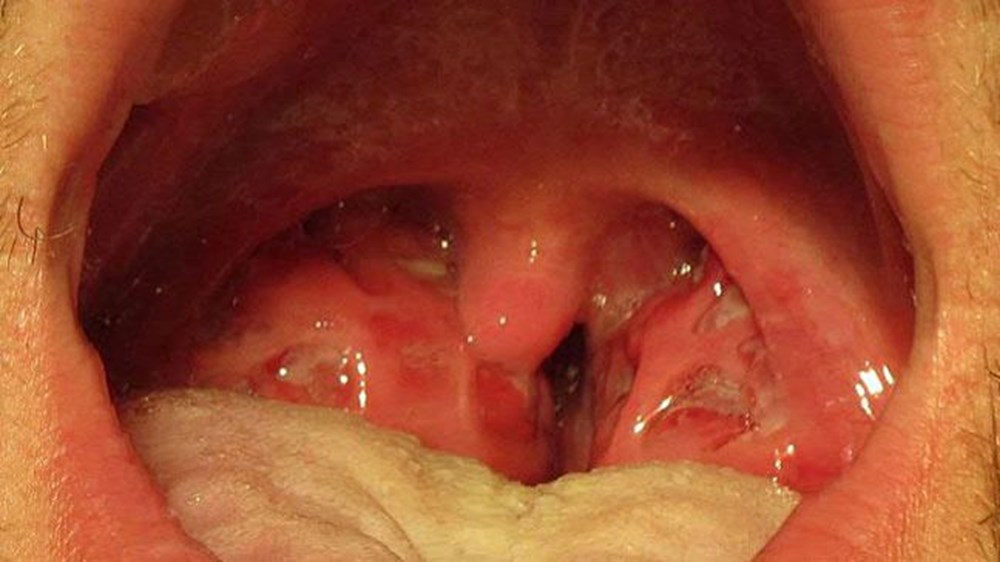

Strep A semptomları arasında yutkunma sırasında ağrı, ateş, beyaz benekli şişmiş bademcikler, şişmiş boyun bezleri, yüksek ateş veya deri döküntüsü yer alıyor.

-Bademcik iltihabı

-Farenjit

-Kızıl

Pysik, grip ile Strep A’yı ayırt etmenin önemli yollarından birinin “çilek dil” adı verilen ve dil üzerinde çıkan beyaz benekler olduğunu söyledi. Pysik, Strep’nın yayılma şekli nedeniyle, genellikle okul ortamlarında ve bakım evlerinde daha yaygın olduğunu ve semptomların ortaya çıkmasını önlemek için “mümkün olduğunca çabuk” antibiyotik almanın önemli olduğunu sözlerine ekledi.